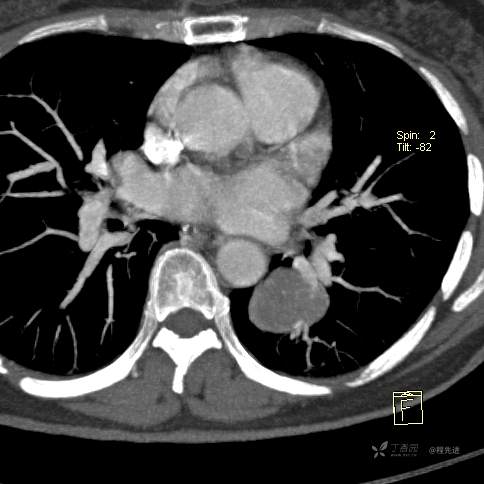

患者性别:女

患者年龄:57岁

简要病史:体检发现

CT增强

平扫CT值约40HU(未上传图像),增强后动脉期CT值约70HU,静脉期CT值约97HU。